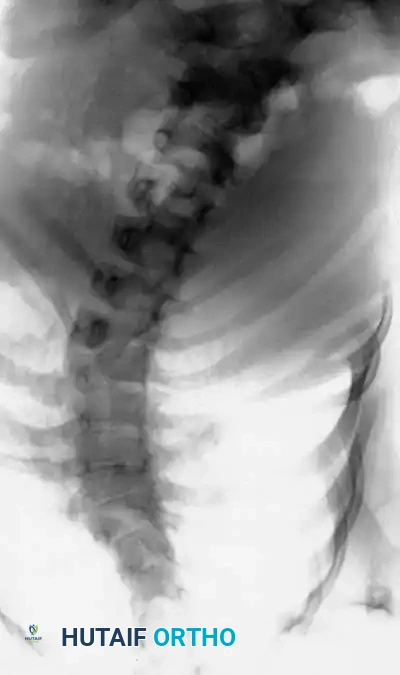

Image

Radiographic examples of progressive congenital curves requiring early intervention.